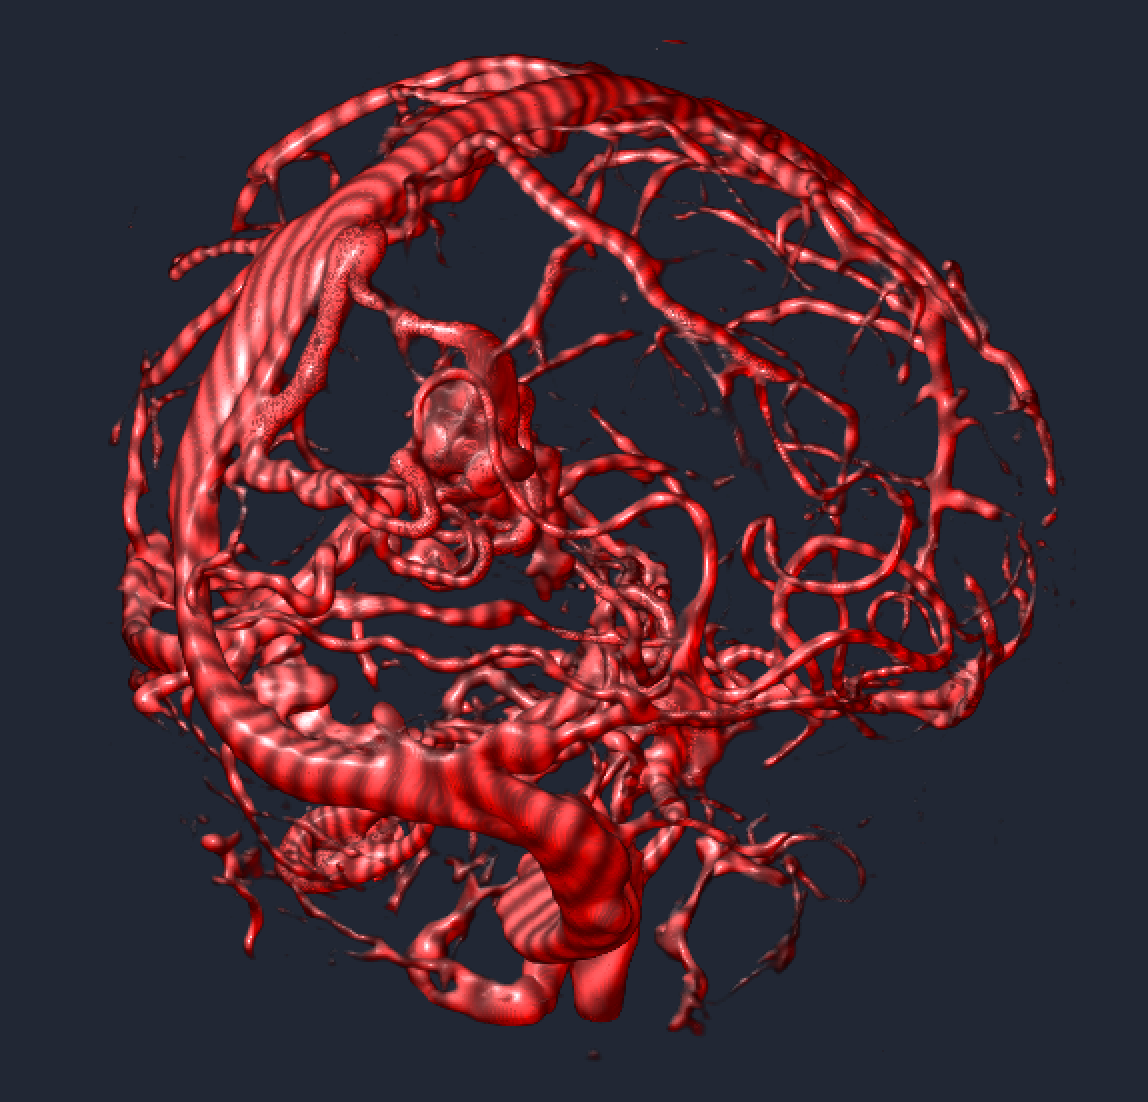

- Provided a proof of concept (python script) for dynamic shader editing in Slicer (see image, video and link to script below)

Proof of concept

Result

Illustrations

| Philips 3D US | Chroma-depth in PRISM | Depth peeling in PRISM |

|---|---|---|

|

|

|

| Edge enhancement in PRISM | Decluttering in PRISM | Volume carving in PRISM |

|---|---|---|

|

|

|

| Blood flow animation in PRISM | ||

|---|---|---|

|